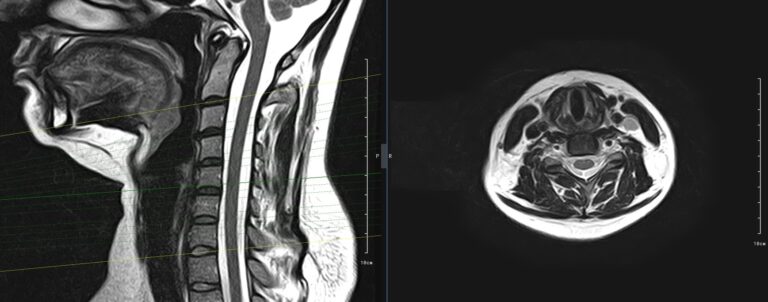

Для того, чтобы оценить состояние шейных позвонков с прилегающими тканями и одновременно визуализировать плечевой сустав, в нашей клинике выполняется комплексное обследование, включающее два протокола: МРТ шейного отдела позвоночника и МРТ плечевого сустава.

Метод МРТ позволяет оценить состояние всех анатомических областей шейного отдела позвоночника: костную структуру позвонков, спинной мозг с отходящими от него нервными корешками и окружающие мягкие ткани. Протокол обследования плечевого сустава включает оценку костной структуры, суставной капсулы, полости сустава с выстилающей его синовиальной оболочкой, связок, сухожилий, мышц и окружающих мягких тканей.

В клинике «Доступная медицина» исследование проводится на современном высокопольном томографе закрытого типа TOSHIBA VANTAGE TITAN 1,5 Тесла с превосходной  разрешающей способностью, которая обеспечивается высокой индукцией магнитного поля. Аппарат выполняет сканирование послойно в различных плоскостях и на основе этого создает 3D-изображения с высочайшей точностью и достоверностью, что позволяет эффективно ставить диагноз и назначать необходимое лечение.